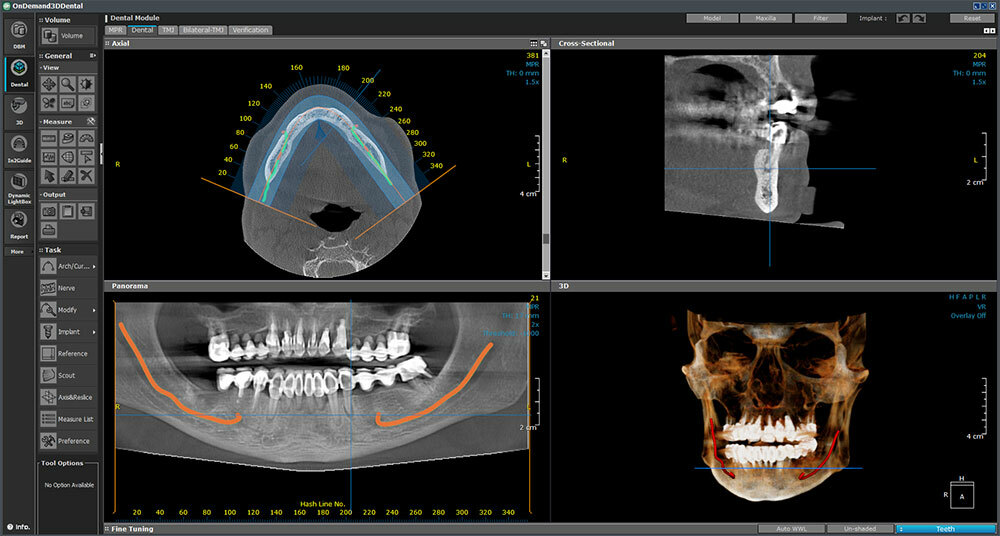

Naš rendgen centar ponosno koristi Dexis OP 3D Pro, uređaj koji omogućava potpuno digitalno i vrlo precizno snimanje.

Ovaj savremeni uređaj pruža jasne i detaljne slike koje olakšavaju dijagnostiku i planiranje terapije. Prednosti korišćenja Dexis OP 3D Pro uređaja su mnogobrojne:

Dexis OP 3D Pro donosi potpuno digitalno rešenje za ortopantomogram (OPG), telediogram, skanogram, bitewing, i 3D snimke vilice, čime pruža sveobuhvatnu podršku dijagnostici za različite stomatološke zahvate i analize.

Bilo da vam je potrebno jednostavno snimanje zuba ili složeniji pregled maksilarnih sinusa i TM zglobova, naš centar je tu za vas.